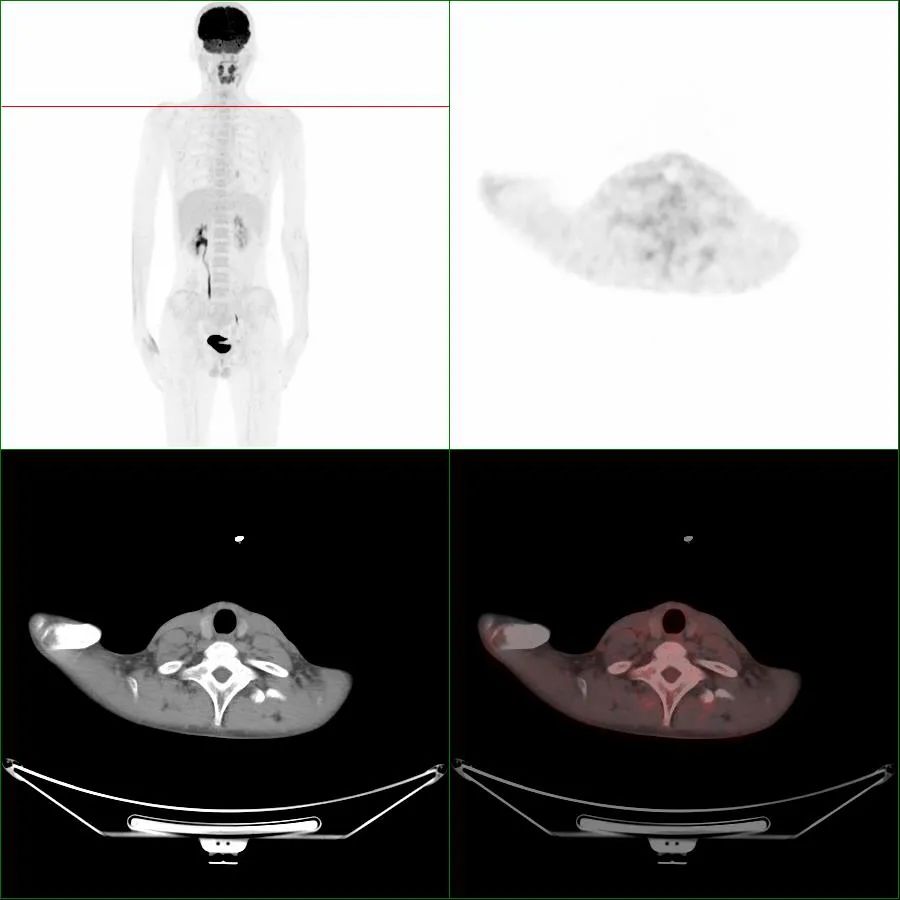

在寒冷环境下,人体为了维持体温,棕色脂肪会迅速地分解和消耗,以释放出能量来维持体温,形成高代谢摄取(图1,箭头),被PET/CT检测到其显影。对读片医生来说,它是伪影,会掩盖该区域的病灶检出,影响对病灶的判断。当对诊断有严重影响时,不得不改期再次进行PET/CT检查,造成不必要的时间和经济损失。

图1 第1次显像,箭头指示为棕色脂肪显影